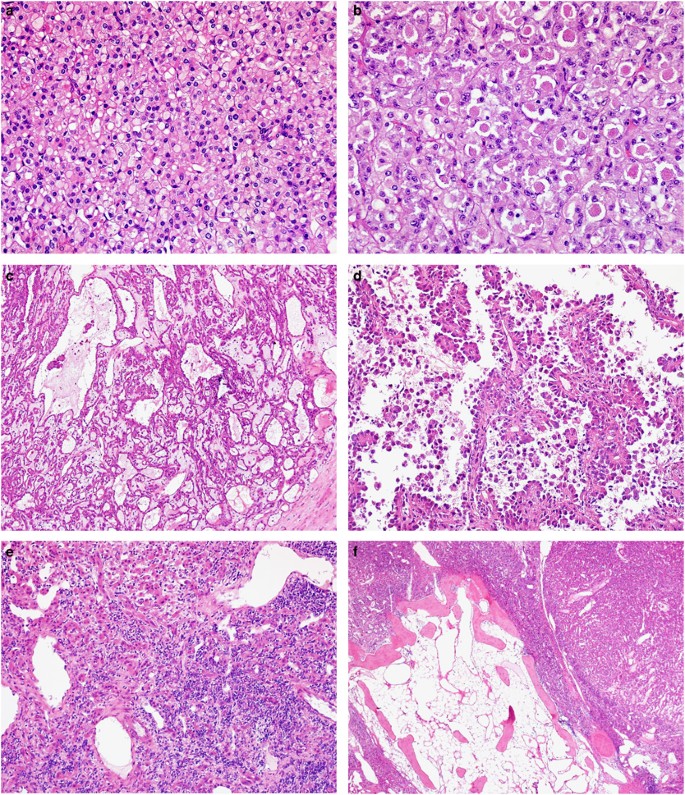

The gross and microscopic features were different in each case and they are presented separately for completeness. A summary of the main histological findings is tabulated in Table 1 (Figures 1 and 2).

At low magnification, tumor 1 was partly surrounded by pseudocapsule and showed a solid architecture (a). At high magnification, the same tumor was composed of eosinophilic cells with central round nuclei and prominent nucleoli (c and d) with scattered foamy macrophages (c). Granular cytoplasmic SDHB staining was present in the non-neoplastic tubules (internal control) but all of the neoplastic cells were negative (b). Intense nuclear labeling for TFE3 was also observed (e). Fluorescence in situ hybridization of the same case showed the green and red signals split apart, demonstrating the TFE3 translocation (f).

Morphologically, sheets of cells with eosinophilic cytoplasm (a) and cytoplasmic inclusion (b) were commonly seen. Some tumors displayed papillary architecture (c) and cystic changes (d). Aggregates of lymphocytes intermixed with tumor cells were observed in two tumors (e). In tumor 3, foci of metaplastic bone were found (f).